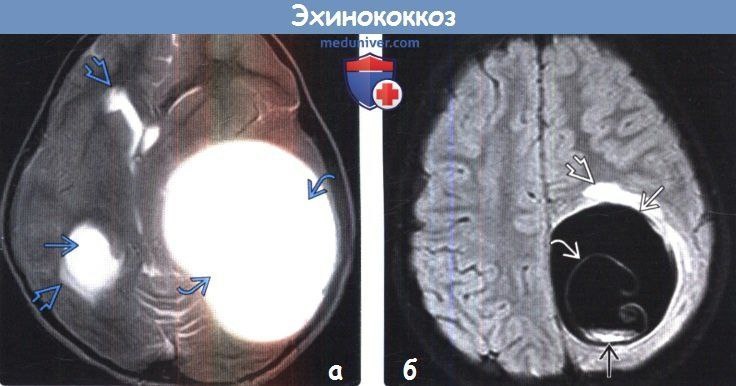

Кстати, на картинке, чтобы запомнилось - киста эхинококка в головном мозге человека. Теперь можно смело пойти и поцеловать своего питомца.